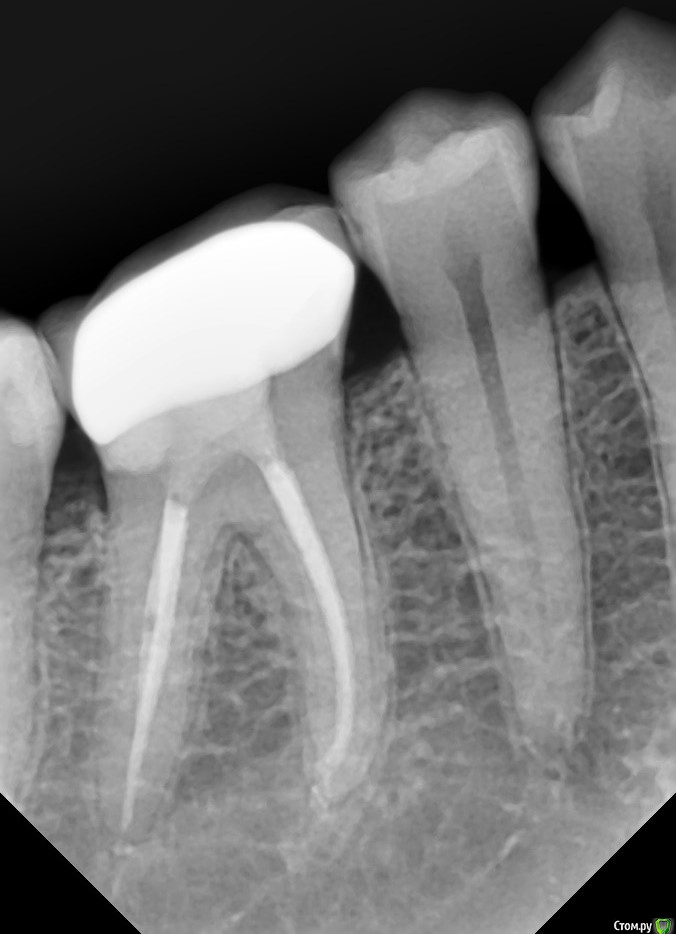

Hans85 Опубликовано 16 января, 2015 Поделиться Опубликовано 16 января, 2015 может есть подобные темы здесь.Как вы относитесь к марджин элевейшен?.Вот одна из моих работ.Делаем ставки господа-сколько прослужит(честно обещаю каждый год выкладывать рентген). Ссылка на комментарий

Doc Опубликовано 17 января, 2015 Поделиться Опубликовано 17 января, 2015 Стесняюсь спросить,что такое мэрджин элевейшин?Ну, это красивое название "переноса уступа" (дословно "подъем края"). Если, как видите на снимке, апроксимально кариес ушел глубоко под десну, то мы уже где-то обсуждали перенос уступа на вкладке, например. Делается вкладка, а уже выше уровня десны прямо на вкладке делается уступ и сажается коронка. Вкладка куда надежнее пломбы, но даже в том случае большинство врачей признало эту методику не адекватной. Ну а про пломбу и говорить нечего. Там количество слабых мест куда больше, а следовательно протекать будет с большей вероятностью. При условии сохранения большого количества твердых тканей такой зуб действительно иногда может продержаться много лет, но скорее как исключение, подтверждающее правило. 2 Ссылка на комментарий

carloss Опубликовано 17 января, 2015 Поделиться Опубликовано 17 января, 2015 В таких случаях как, на рентгене, я даже удлинение не делаю - достаточно пройтись коагулятором или лазером.. и повторить то же самое на этапе цементировки 3 Ссылка на комментарий